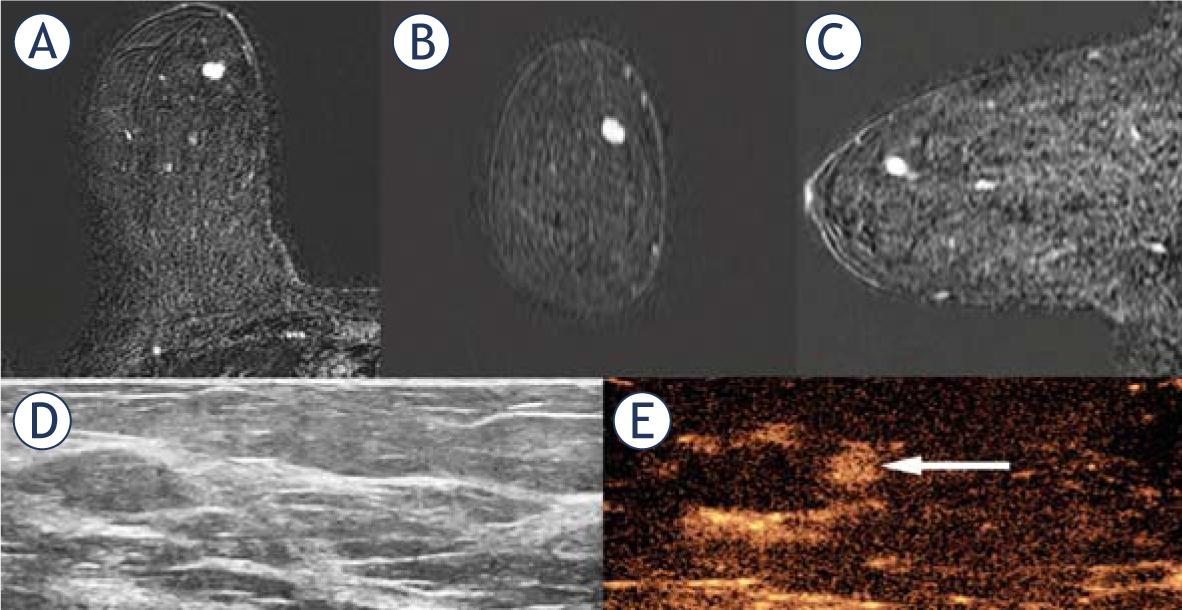

| 1 | 71 | Preoperative local staging | Mass, round, circumscribed, washout kinetic curve | 6 mm | Positive | CEUS-guided CB | CB: Low grade DCIS Final: Low grade DCIS. 3 mm |

| 4 | 54 | Preoperative local staging | Mass, round, circumscribed, heterogeneous, washout kinetic curve | 7 mm | Positive | CEUS-guided clip placement | Final: Intermediate grade IC NST. 5 mm |

| 8 | 61 | Preoperative local staging | Mass, oval, irregular, washout kinetic curve | 10 mm | Positive | CEUS-guided CB | CB: Low grade DCIS Final: low grade IC NST 6 mm and Low grade DCIS 5mm |

| 9 | 53 | Preoperative local staging | Mass, oval, irregular, washout kinetic curve | 16 mm | Positive | CEUS-guided CB | CB: High grade IC NST Final: High grade IC NST. 13 mm |